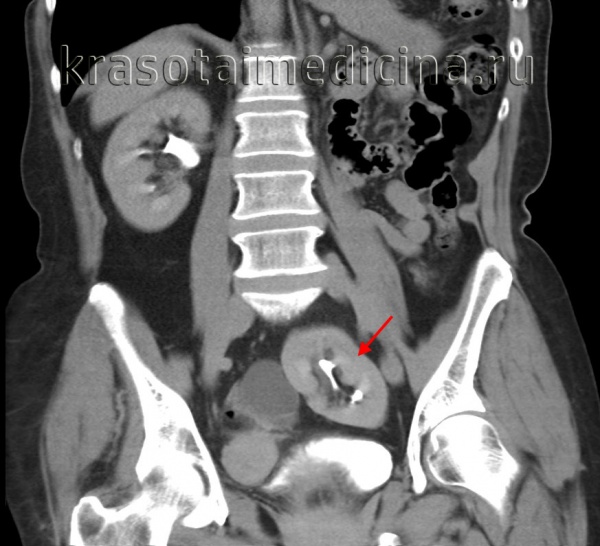

1. Общие сведения:

• Критерии диагностики:

о Пустое почечное ложе

о Морфология имеющейся почки изменена

• Морфология:

о Поворот эктопической почки зачастую не завершен:

- Угол поворота почечной лоханки определяется тем, в какой момент эмбриогенеза произошло сращение

о Мочеточник пересекает срединную линию и впадает в мочевой пузырь в типичном месте

о Подвиды:

- Одностороннее сращение, нижняя эктопия

- Сигмовидная или S-образная

- В форме лампы или пирога

- L-образная или «тандем»

- В форме диска, щита или пончика

- Одностороннее сращение, верхняя эктопия

о Морфология имеющейся почки изменена:

- В 90% случаев перекрестной эктопии почки сращены:

В остальных случаях несросшиеся почки принимают разную конфигурацию

- При сращении образуется атипичная двудолевая почка крупных размеров

о Расположена более каудально, повернута под большим углом, чем подковообразная почка

• ЦДК:

о На стороне морфологически измененной почки имеются две почечные артерии

о Источники кровоснабжения обеих почек вариабельны:

- Аорта на любом уровне

- Подвздошная артерия